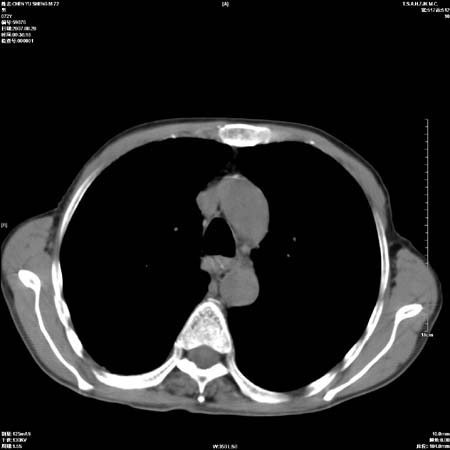

男性,72岁,既往肺结核,今复查。无前片对比。

纵隔窗

右侧中央型肺癌伴中叶不张可能性大,建议增强扫描.右上肺陈旧性肺结核.慢性支气管炎伴肺气肿.右侧少量胸腔积液.

右侧中央型肺癌伴中叶不张可能性大,建议纤支镜检查.右上肺陈旧性肺结核.肺气肿。

典型右肺中心型肺癌

右侧中央型肺癌伴肺不张可能性大,建议增强扫描.右上肺陈旧性肺结核.慢性支气管炎伴肺气肿.右侧少量胸腔积液.

右肺中心型肺癌

右侧中央型肺癌.上肺陈旧性肺结核.

1右侧中央型肺癌伴中叶不张2右侧少量胸腔积液3右上肺陈旧性肺结核

1.右肺中心性肺癌并右肺中叶综合征2。右侧胸腔少量积液3。右肺上叶结核球已钙化,4。慢支伴肺气肿

右侧中央型肺癌伴中叶不张可能性大,建议纤支镜检查.右上肺陈旧性肺结核.肺气肿。

右侧中央型肺癌伴中叶不张可能性大,建议增强扫描.右上肺陈旧性肺结核.慢性支气管炎伴肺气肿.右侧少量胸腔积液.

右侧中央型肺癌伴中叶不张

右肺中央型肺癌伴右肺中叶不张。

右上肺陈旧性肺结核。

支持右肺中心型肺癌并中叶不张,右上肺陈旧性肺结核钙化,右侧少量胸腔积液。

支持右侧中央型肺癌伴中叶不张可能性大,建议增强扫描.右上肺陈旧性肺结核.慢性支气管炎伴肺气肿.右侧少量胸腔积液.

支持 1右侧中心型肺癌伴中叶不张2右侧少量胸腔积液3右上肺陈旧性肺结核4双肺局限性肺气肿

1,右侧中央型肺癌.

2,右上肺陈旧性肺结核.

1.右侧中央型肺癌伴中叶不张,建议纤支镜检查.

2.右上肺陈旧性肺结核.

3.肺气肿。

4.右侧少量胸腔积液.

右侧中央型肺癌伴中叶不张并纵隔淋巴结增大,建议增强扫描.右上肺陈旧性肺结核.慢性支气管炎伴肺气肿.右侧少量胸腔积液。

右肺中心型肺癌并肺不张,陈旧性肺tb.慢支,肺气肿.

陈旧性肺结核.慢性支气管炎伴肺气肿,中央型肺癌伴中叶不张。

右侧中央型肺癌伴中叶不张可能性大;右上肺陈旧性肺结核.慢性支气管炎伴肺气肿

陈旧性结核是存在,但真正致命的却是右侧中心型肺癌。